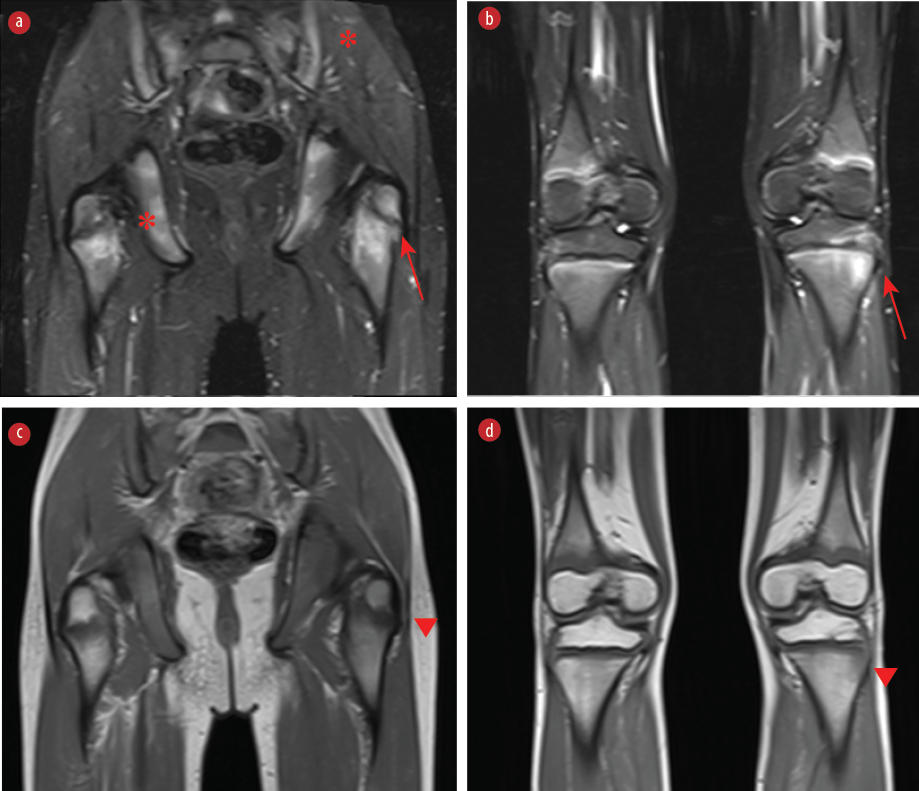

He underwent a whole-body magnetic resonance imaging (MRI) [Figure 1]. Informed consent was obtained from the patient’s parent.

Figure 1: Coronal MRI images of the pelvis/proximal femur, distal femur and proximal tibia. (a, b) Edema is seen in the periphyseal regions of the femur and tibia on short-tau inversion recovery images (red arrows). (a) Asymmetric involvement of the pelvic bones and sacroiliac joints (*) is also present. (c, d) Corresponding low-signal changes are noted on T1-weighted images (arrowheads).

These differential diagnoses were ruled out in our patient based on clinical features and the absence of systemic symptoms suggestive of malignancy or infection, negative blood cultures, and MRI findings (e.g., multifocal, symmetric lesions with no abscess or sequestrum). Whole-body MRI revealed bilateral asymmetric subchondral bone marrow oedema in the sacroiliac joints. The femurs showed peri-physeal edema on the left near the greater trochanter and edematous changes in the peri-physeal metaphysis of the femur on both sides, and similar changes in the proximal tibia bilaterally, in keeping with a diagnosis of CRMO.